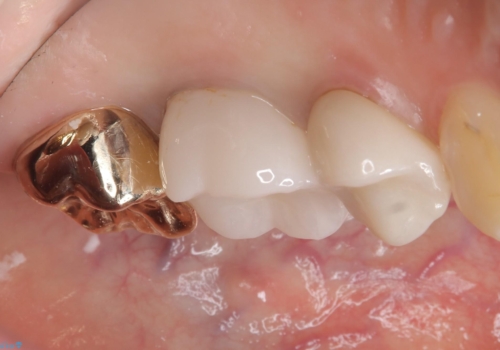

メタルインレーを除去したところ、残存歯質量が少なく破折のリスクを説明し、ゴールドクラウンでのやり替えとなりました。

保険のメタルインレーから二次う蝕予防(保険のメタルインレーは腐食しやすかったり、適合があまり良くなかったりで二次的にう蝕がインレー下で広がってしまうことが多々あります。)のためのやり替えだったため、材料としてセラミックとゴールドを提案したところ、展延性に優れ違和感の少ないゴールドを選択されました。